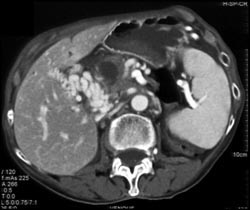

Cholangiocarcinoma